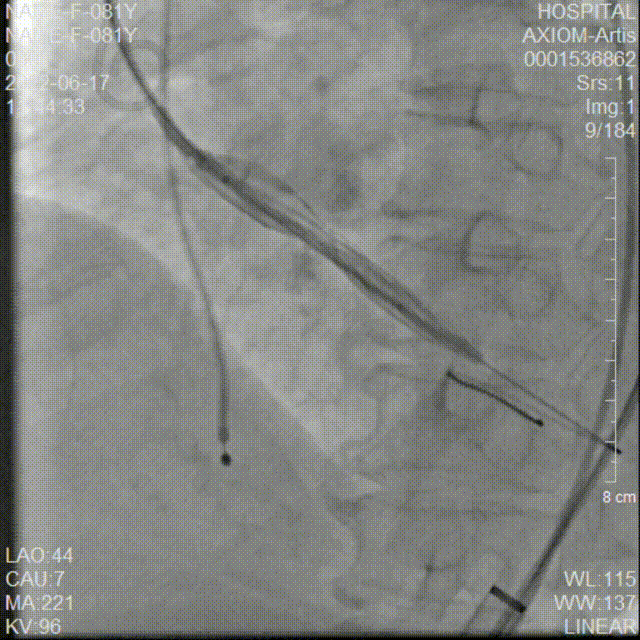

AV26瓣膜定位

AV26瓣膜第一次释放到工作位

第一次释放到工作位造影检查

AV26瓣膜第二次释放到工作位

第二次释放到工作位造影检查

AV26瓣膜第三次释放到工作位

第三次释放到工作位造影检查

AV26瓣膜第四次释放到工作位

第四次释放到工作位造影检查